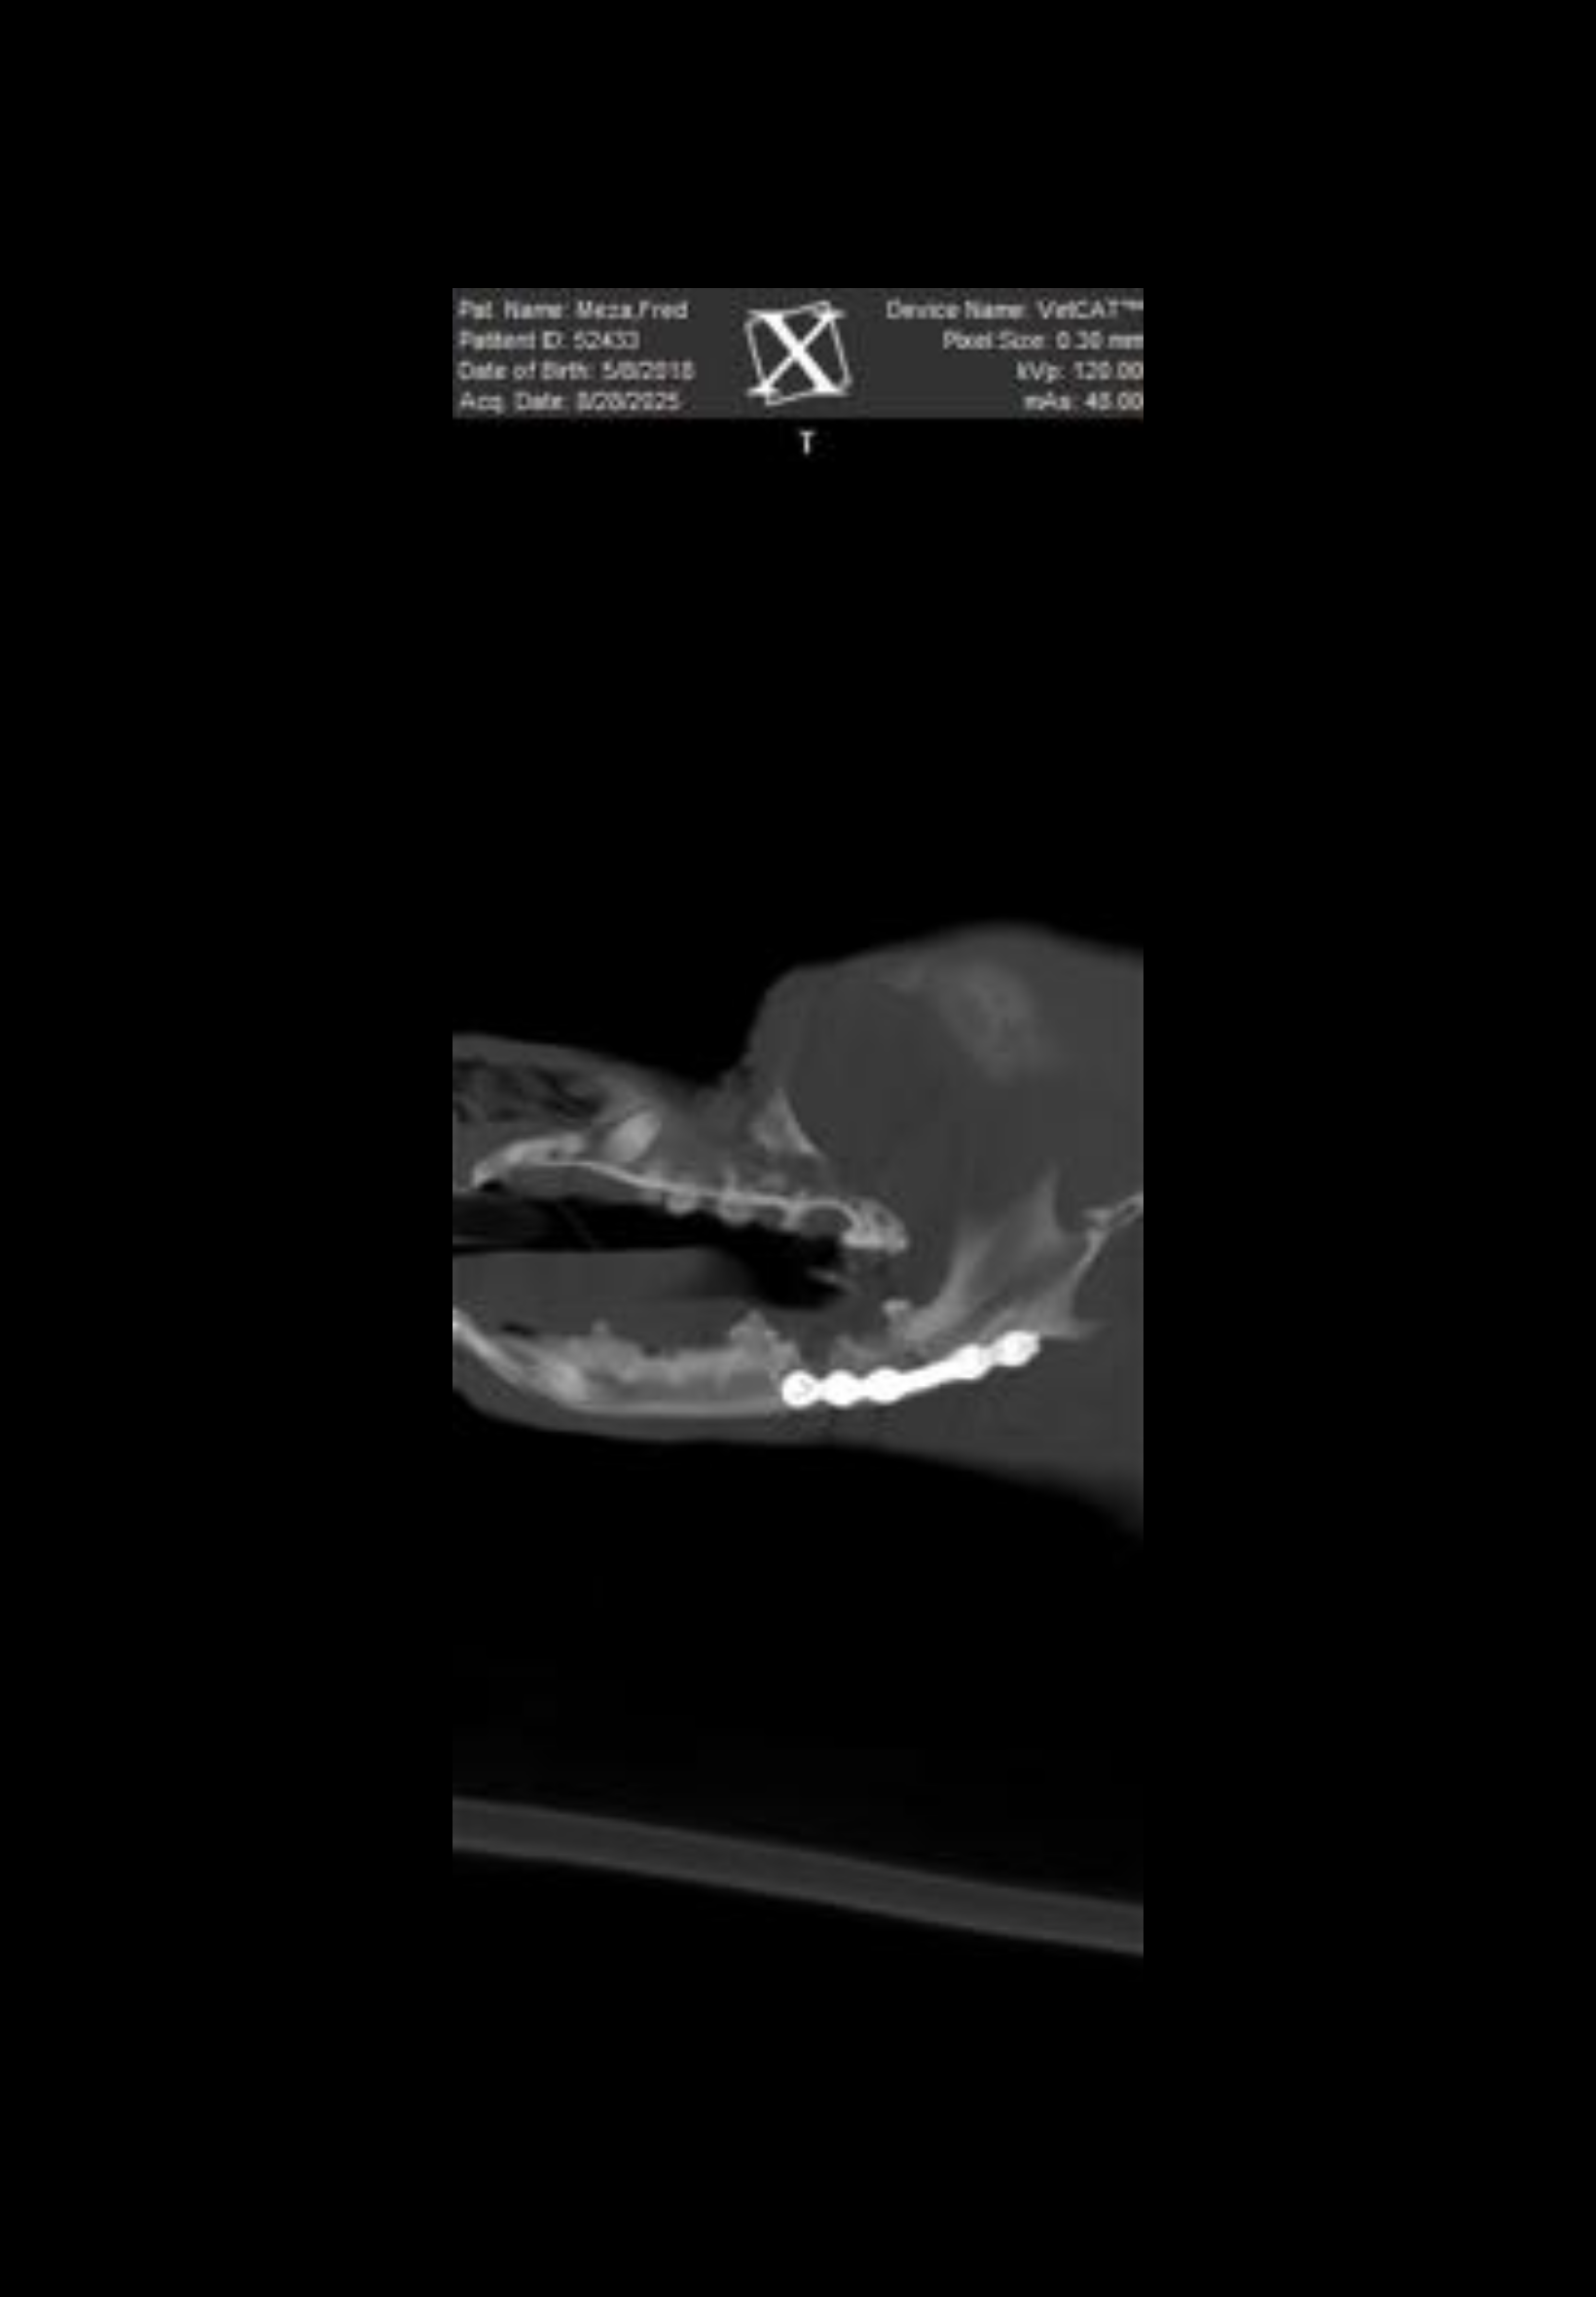

While doing laundry with Fred (who was on a leash and wearing a harness), an unleashed pitbull ran in and viciously attacked him, biting him directly on the face. The result? Fred’s jaw was fractured in the attack, and he was left bleeding and in excruciating pain. I had to pull Fred from the dog’s mouth myself, while the other dog's owner stood by and did nothing to help.

Fred was rushed to MASH Animal Hospital , where he underwent emergency treatment to stabilize his condition. He required major jaw surgery, including the placement of a metal plate to try to repair the fracture.

But now, the situation has taken a turn: The metal plate failed and Fred needs another $3,500 surgery to remove the plate and prevent further complications.